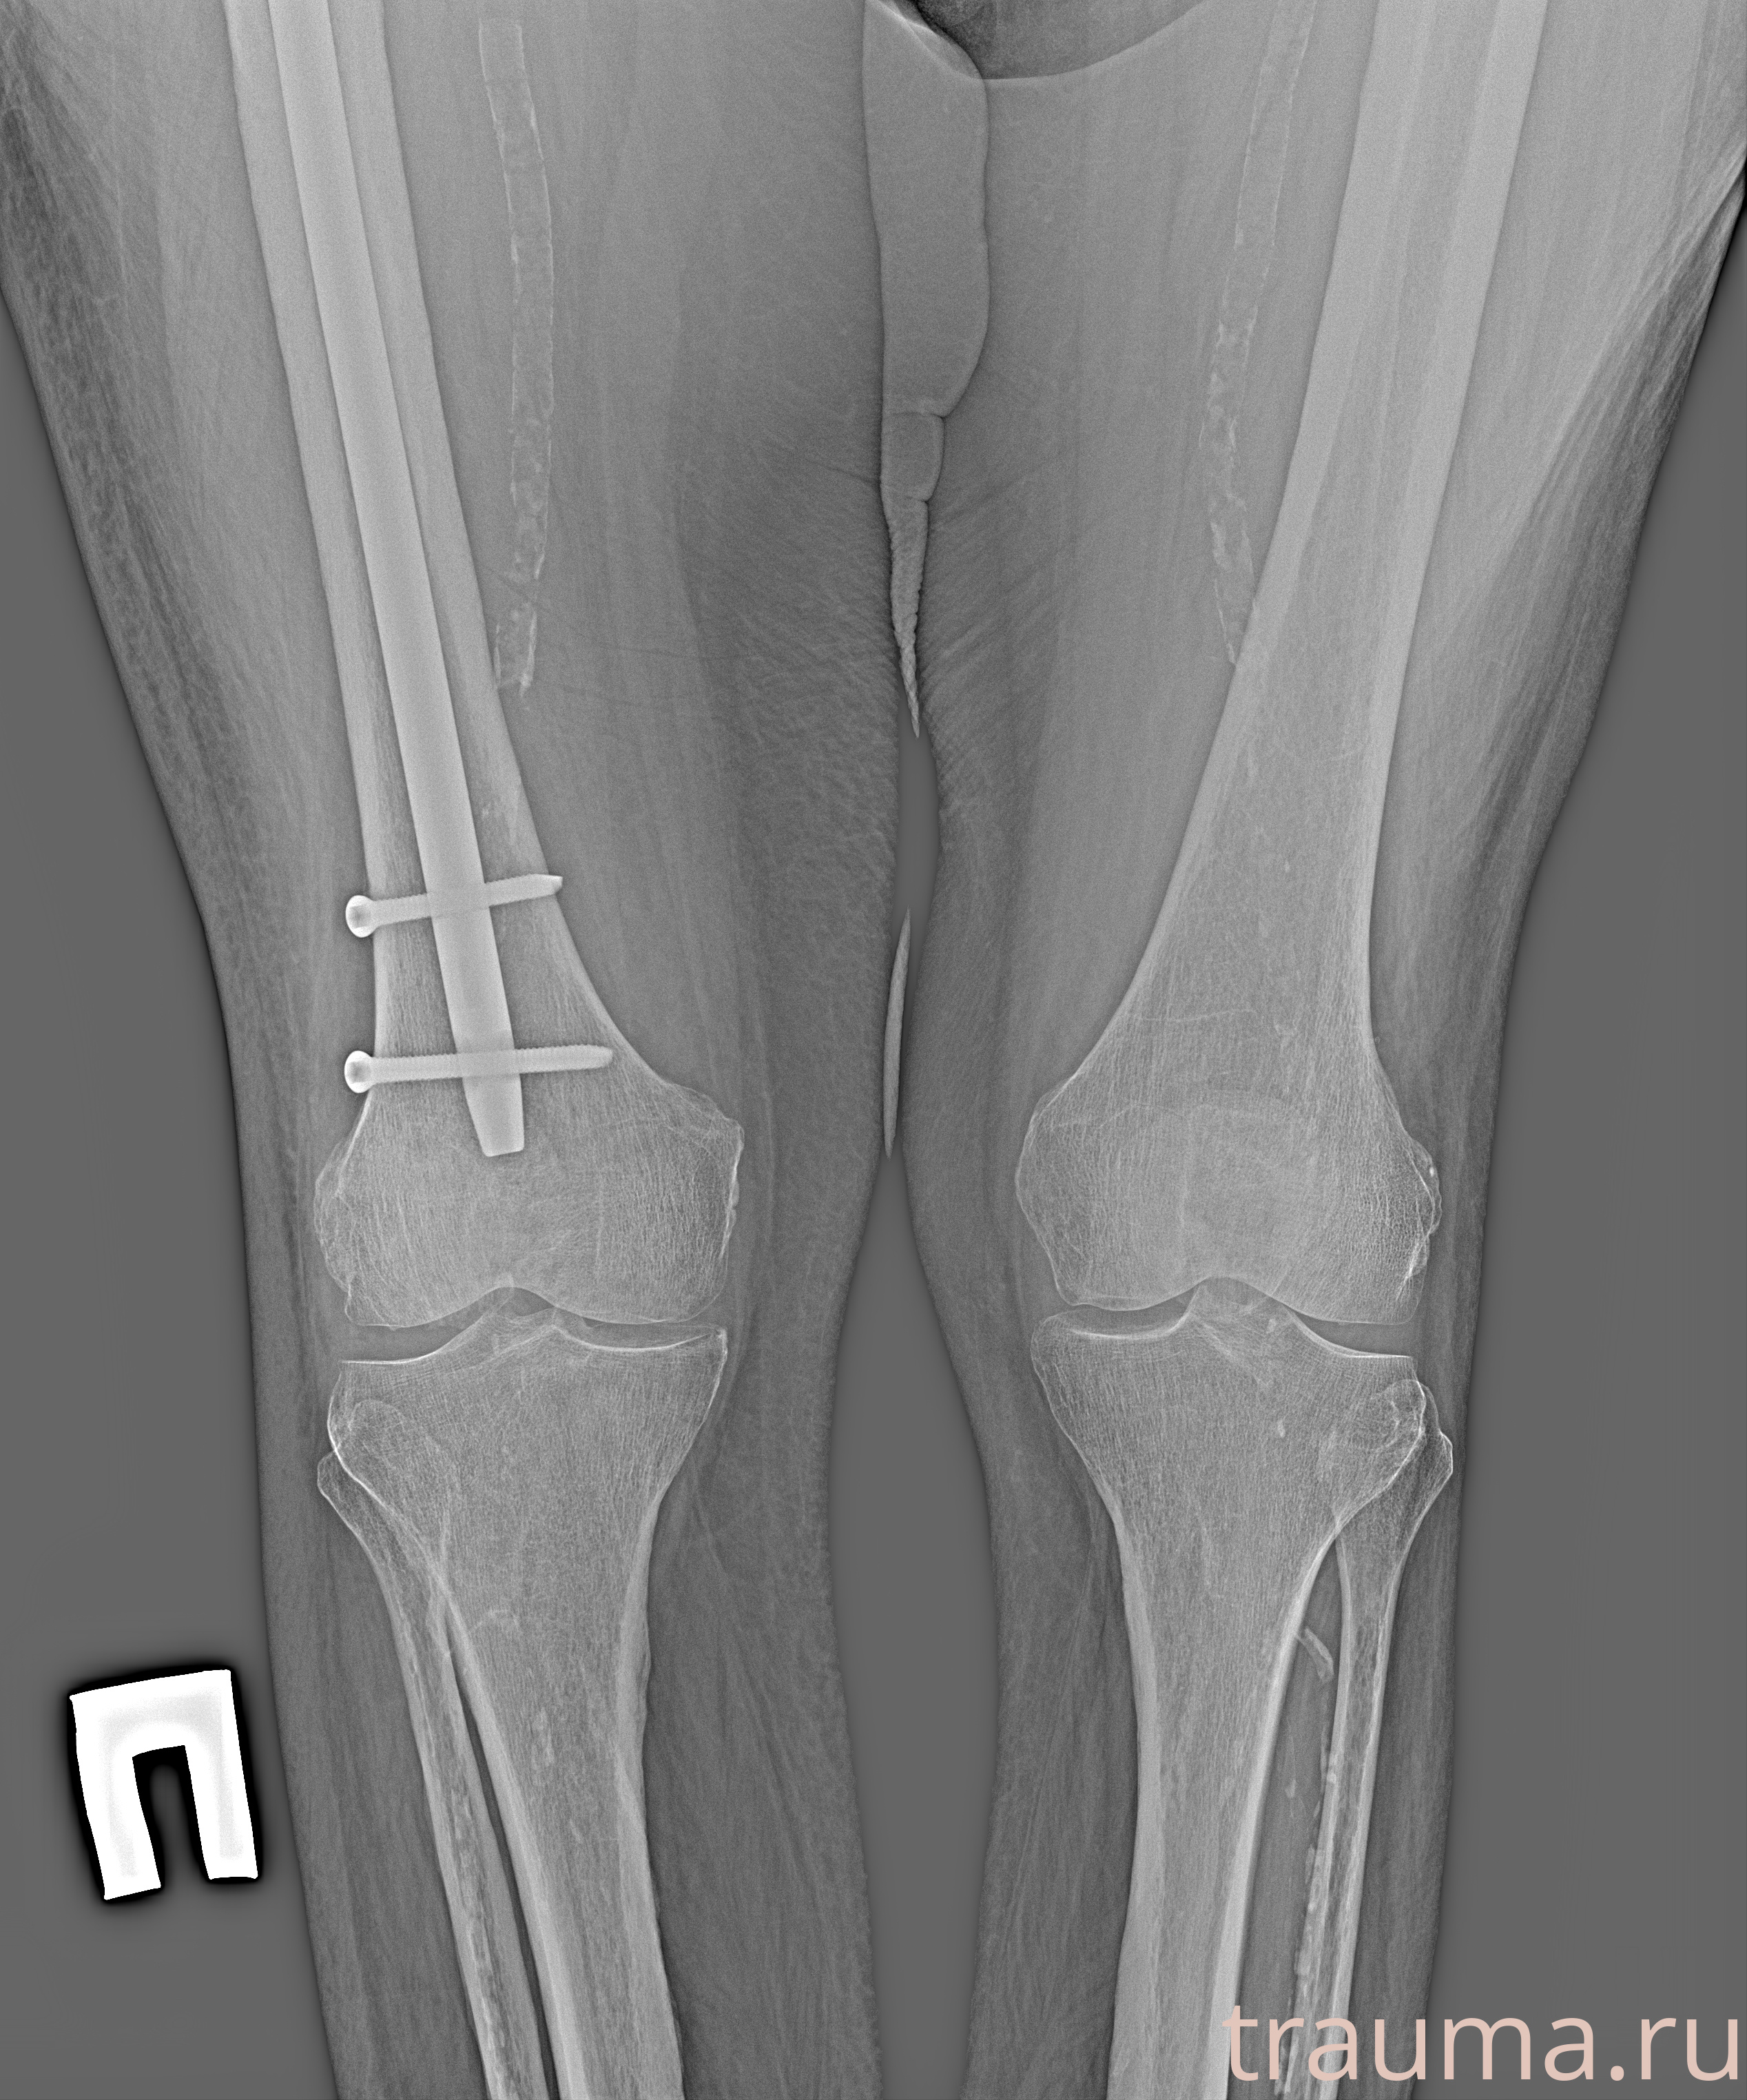

Рентгенограммы